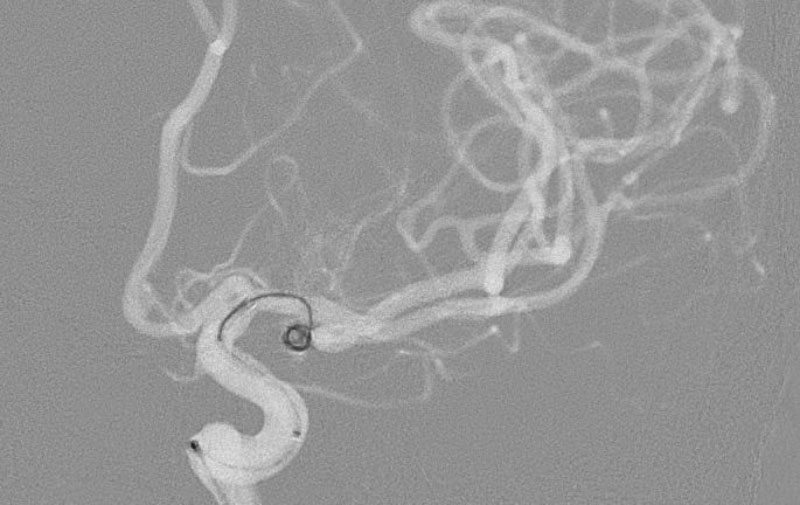

'25年11月

くも膜下出血

左中大脳動脈瘤破裂

40代

救急外来

No.1596 手術前

No.1596 手術中

No.1596 手術後